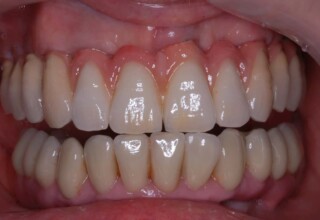

Ολική Στοματική Αποκατάσταση σε Εμφυτεύματα με διαφορετική προσέγγιση στην Άνω και Κάτω Γνάθο

Κάτω γνάθος: εξαγωγές, άμεση τοποθέτηση εμφυτευμάτων και άμεση φόρτιση(την ίδια ημέρα) με προσωρινή γέφυρα

Άνω γνάθος: σταδιακές εξαγωγές, σταδιακή τοποθέτηση εμφυτευμάτων και σταδιακή ενσωμάτωση τους στην προσωρινή γέφυρα ώστε η ασθενής να μην μείνει ούτε μια ημέρα χωρίς αποκατάσταση. Στόχος η συνεχής λειτουργική και αισθητική αποκατάσταση της ασθενούς χωρίς άμεση φόρτιση των εμφυτευμάτων λόγω ανατομικών ιδιαιτεροτήτων.

Χρησιμοποιήθηκαν παλαιές χαμογελαστές φωτογραφίες της ασθενούς γιατί είχε χαθεί τελείως το φυσικό σχήμα των δοντιών εξαιτίας των πολλαπλών προσθετικών προσπαθειών που είχαν γίνει στο παρελθόν. Μεταφέρθηκε στην προσωρινή γέφυρα η σχέση των φυσικών δοντιών μεταξύ τους άλλα και με τα χείλη. Δοκιμάστηκε η φώνηση και η μάσηση με δυο διαφορετικές προσωρινές άνω γέφυρες και εκτιμήθηκε η αισθητική απόδοση τους. Αφού επιτεύχθηκαν σε βαθμό ικανοποιητικό η φώνηση και η αισθητική εμφάνιση της οδοντοφυΐας, η προσωρινή αποκατάσταση χρησιμοποιήθηκε ως οδηγός για την τελική.

Αρχικό

Ενδιάμεσο

Τελικό